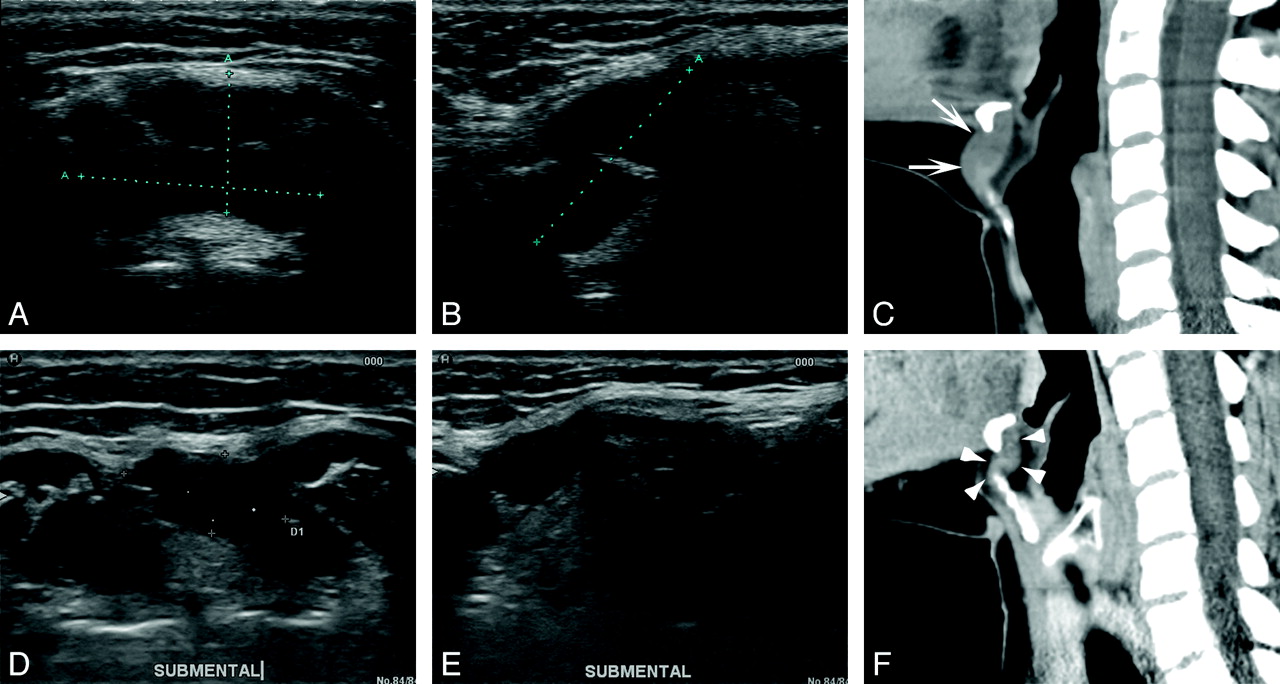

A 41-year-old woman (patient 10). Axial (A) and longitudinal (B) sonograms show the TGDC in a suprahyoid location (2.0 × 2.3 × 3.1 cm; volume, 7.46 mL) filled with fluid. Axial (C) and longitudinal (D) sonograms obtained 13 months after EA show marked shrinkage of the TGDC. (0.35 × 0.6 × 0.76 cm; volume, 1.08 mL; volume reduction, 85.5%)

The mean clinical follow-up period of 11 patients was 14.4 ± 6.9 months (range, 3–29 months). The mean follow-up period of 10 patients who underwent US examinations was 13.6 ± 8.1 months (range, 3–29 months). The mean volume reductions at 0–6, 6–12, 12–29 months, and last follow-up examinations were 67.3% ± 24.6%, 62.1% ± 28.5%, 75.4 ± 24.3%, and 81.3% ± 22.3%, respectively. Technical success (volume reduction of >50% in US examination) was achieved in 8 of 10 patients (Figs 1 and 2). At last follow-up examinations, the volume of the treated TGDCs had decreased significantly from 6.0 ± 8.4 mL to 0.36 ± 0.38 mL (P = .005). Also the mean symptoms and cosmetic-grading scores had improved significantly from 4.0 ± 1.0 to 0.7 ± 1.0 (P = .005) and from 3.9 ± 0.3 to 1.5 ± 0.8 (P = .003), respectively.